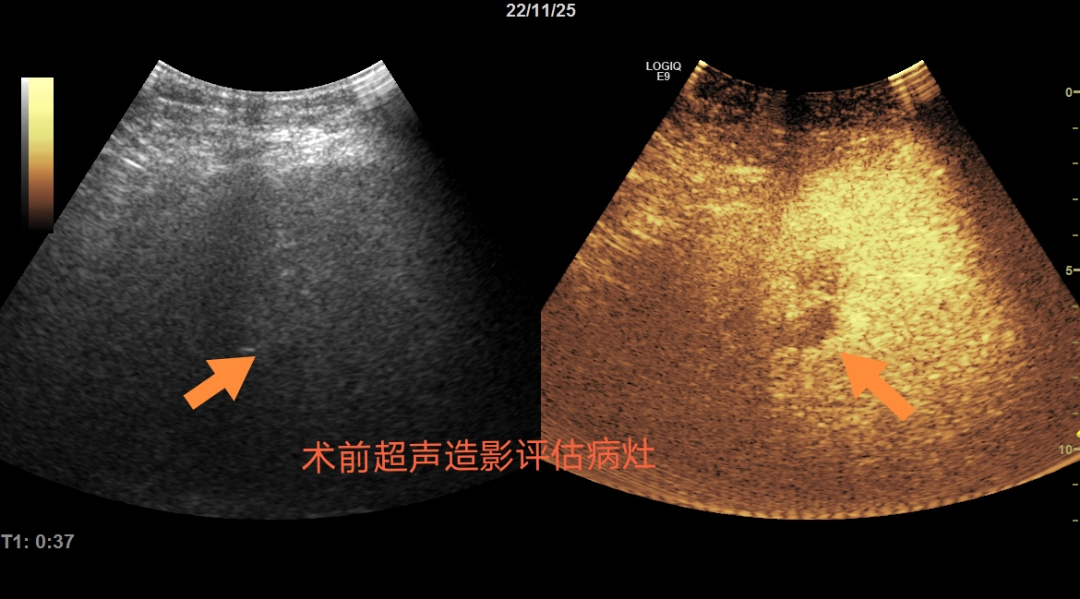

察觉到P女士的顾虑以及她不想再进行二次手术的意愿后,消化内科的管床医生多次与任宏义谈论病情,在请教罗鸿昌教授仔细评估后认为可以采用超声引导下微波消融技术治疗患者的肝脏转移灶,而且术后恢复快,疗效好。这对于P女士及家属来说无疑是最好的消息。任宏义向患者及家属详细介绍了微波消融的方法、风险、注意事项及并发症等,罗鸿昌教授和任宏义对P女士的病情进行了术前讨论及严谨的手术设计

手术当天,从术前准备到手术结束,历时约50分钟。术后再次进行肝脏超声造影显示P女士肝脏转移灶达到了完全热消融,术后第二日患者即可下床活动,术后恢复2-3天即可出院。